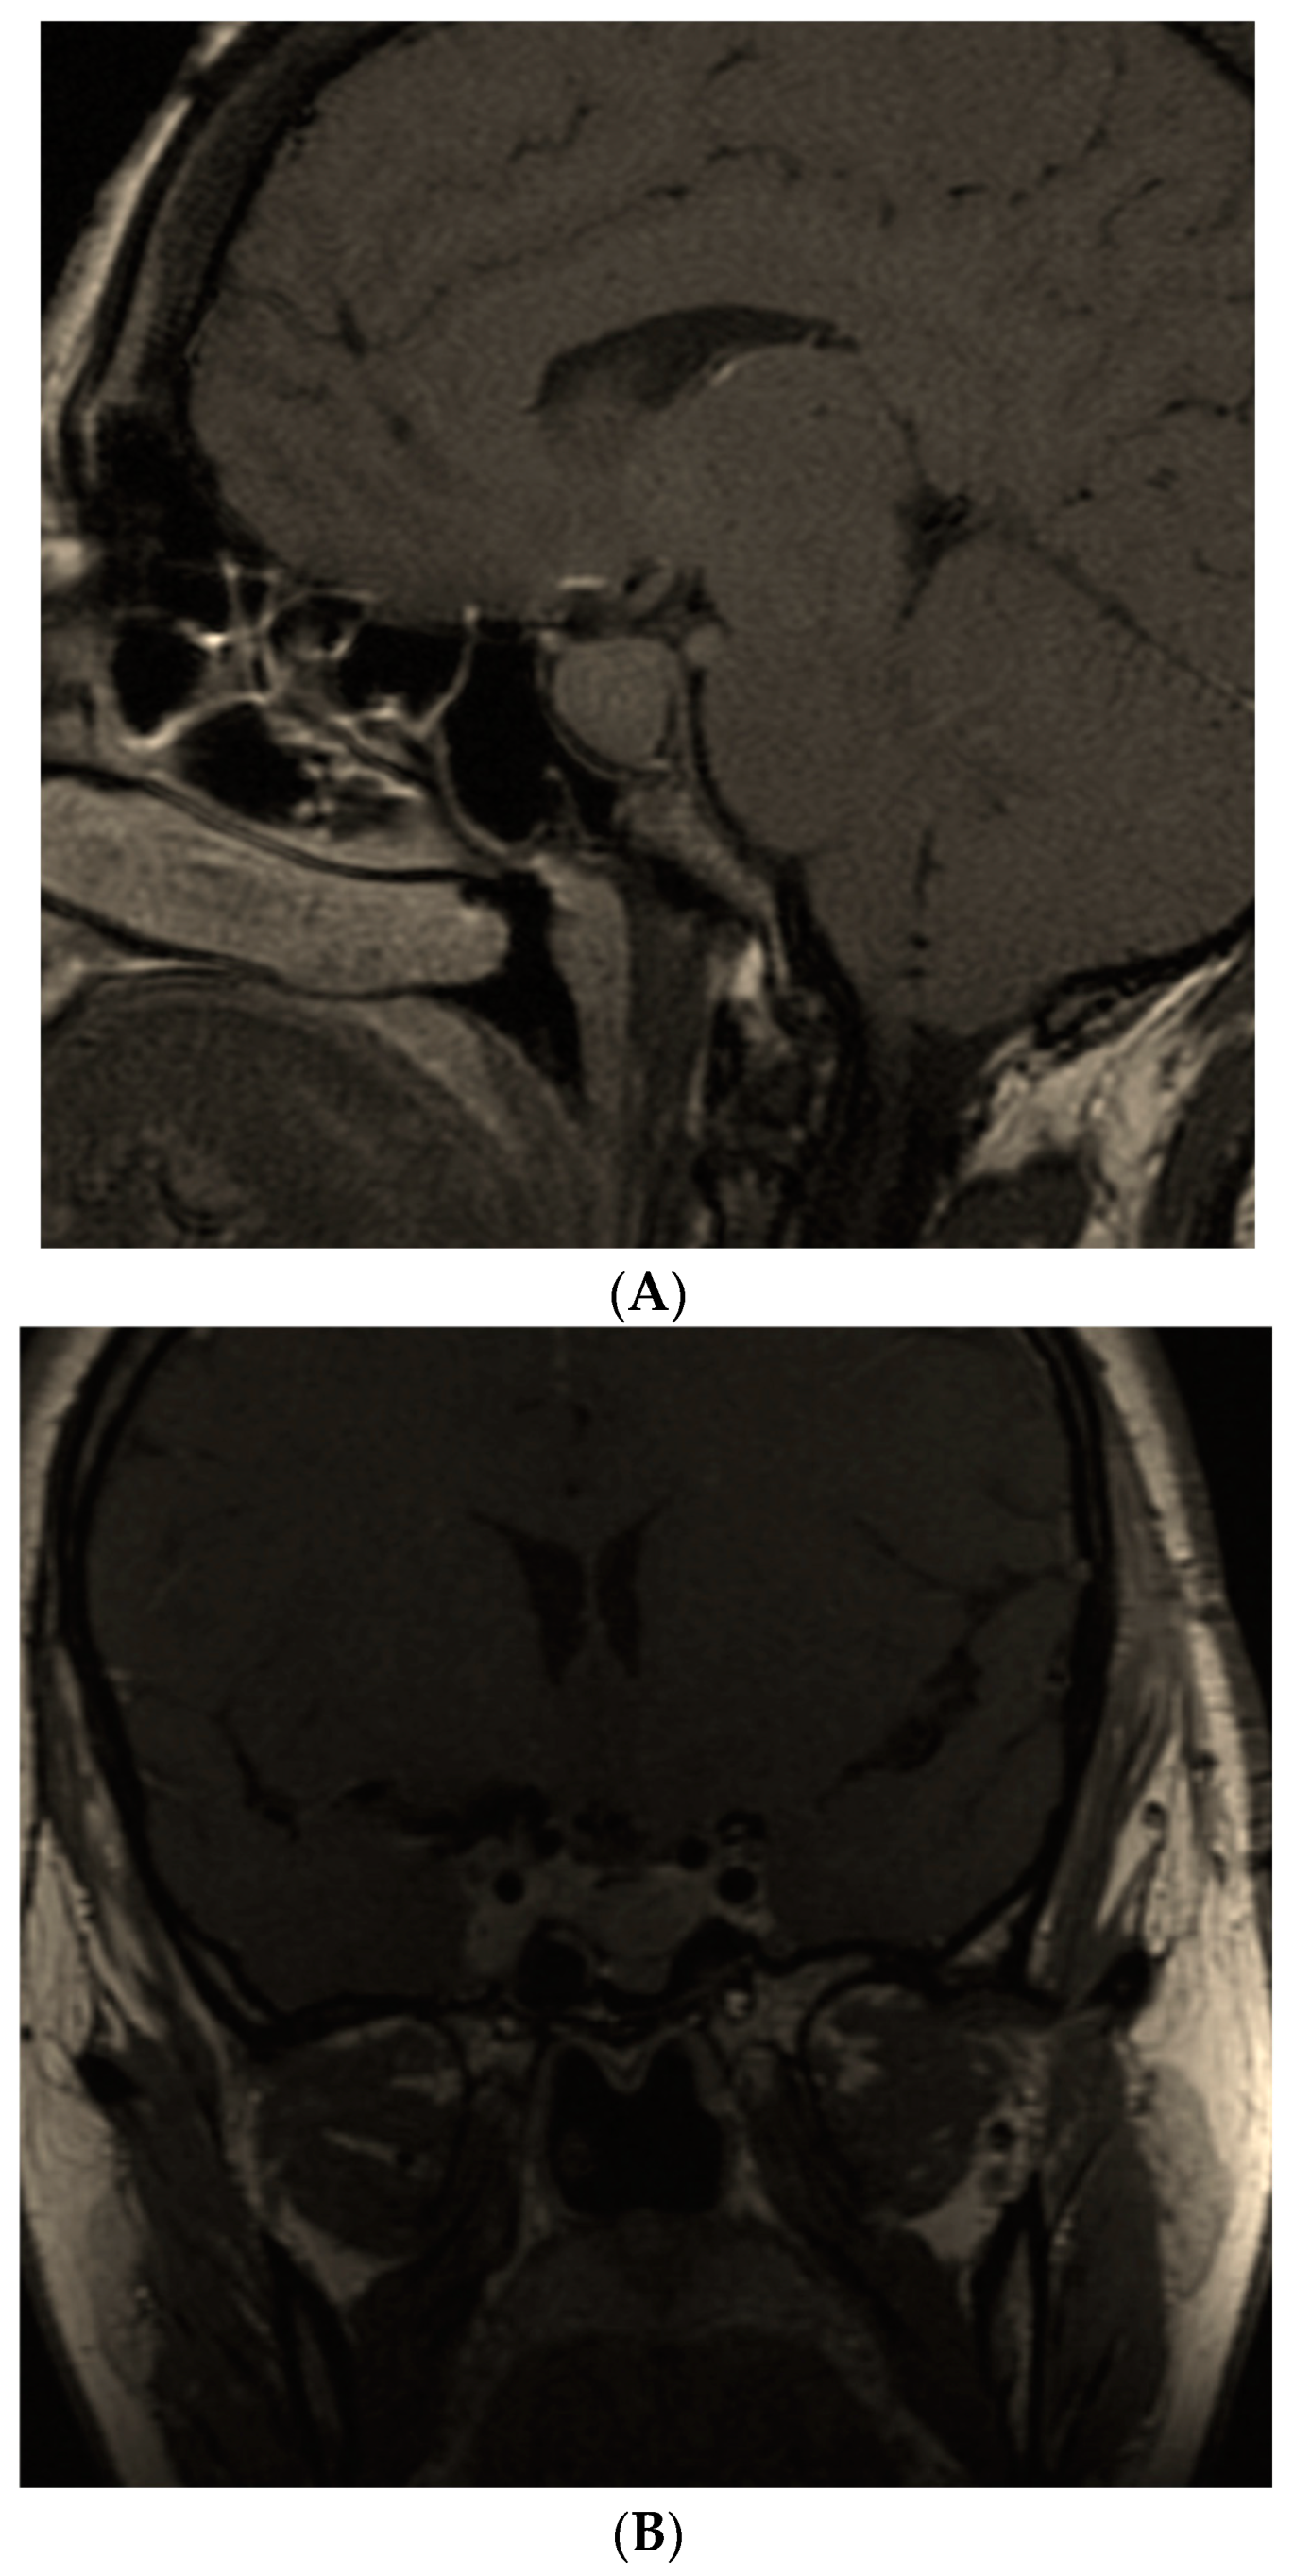

- Hannon, A.M.; Frizelle, I.; Kaar, G.; Hunter, S.J.; Sherlock, M.; Thompson, C.J.; O’Halloran, D.J.; Irish Pituitary Database Group. Octreotide use for rescue of vision in a pregnant patient with acromegaly. Endocrinol. Diabetes Metab. Case Rep. 2019, 2019, 19-0019. [Google Scholar] [CrossRef] [PubMed]

- Dicuonzo, F.; Purciariello, S.; De Marco, A.; Guastamacchia, E.; Triggiani, V. Inoperable Giant Growth Hormone-secreting Pituitary Adenoma: Radiological Aspects, Clinical Management and Pregnancy Outcome. Endocr. Metab. Immune Disord. Drug Targets 2019, 19, 214–220. [Google Scholar] [CrossRef]